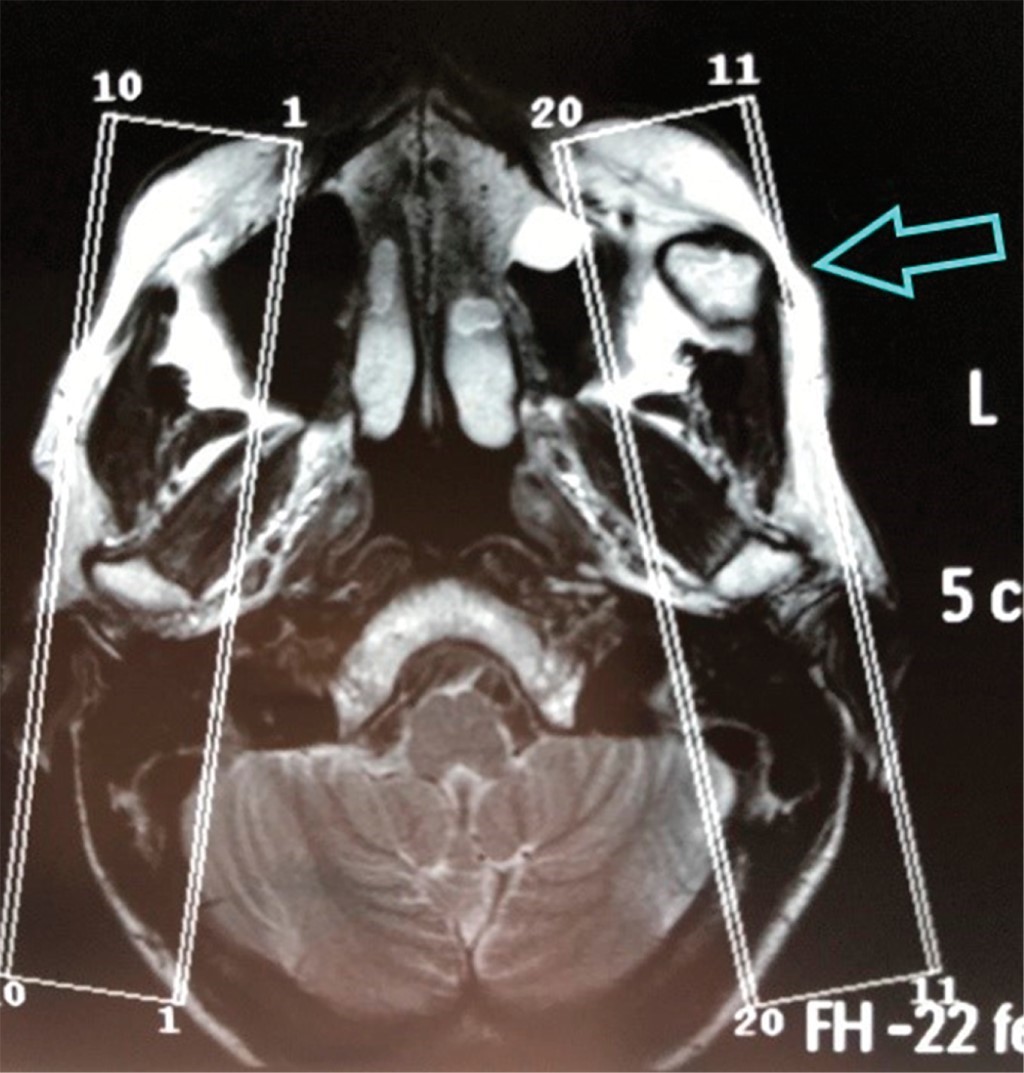

Se solicita resonancia magnética nuclear (RMN) y CBCT sospechando trastorno temporomandibular intracapsular (Figuras 3 y 4).

En la RMN se observa una lesión en la apófisis coronoides del lado izquierdo (Figura 4). En la ciudad de Bahía Blanca, Buenos Aires, Argentina donde desarrollamos nuestra práctica, no contamos con tomógrafo computarizado de haz cónico de Fov amplio, por lo tanto, se solicita una tomografía computarizada multislice, en la cual se verifica una lesión tumoral en la apófisis coronoides izquierda con forma de hongo, que se introduce entre el arco cigomático y el maxilar desplazando ambas estructuras (Figuras 5 y 6).

Figura 4